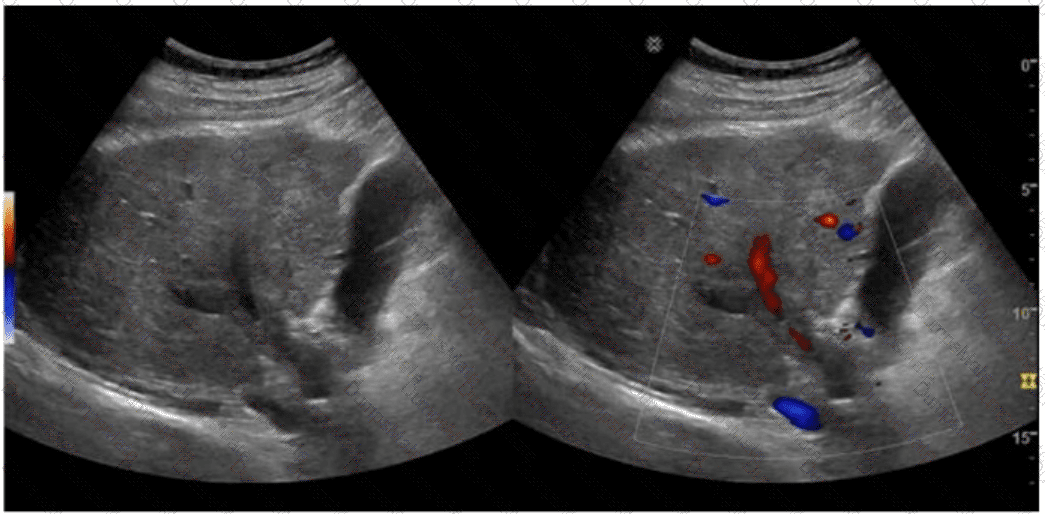

Questions 29

Which vascular condition is most likely associated with the sonographic findings demonstrated in this image?

AB-Abdomen Question 29

Options:

A.

Budd-Chiari syndrome

B.

Splenic artery aneurysm

C.

Recanalized umbilical vein

D.

Median arcuate ligament syndrome